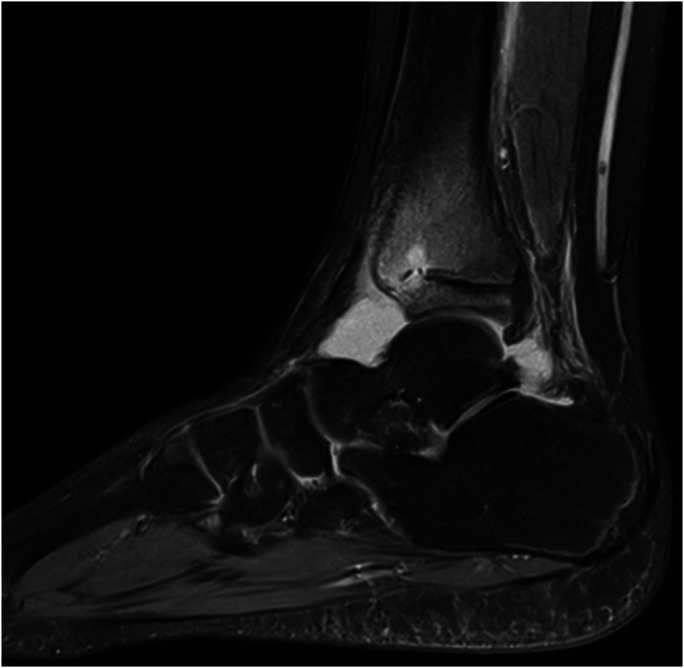

Abstract Image